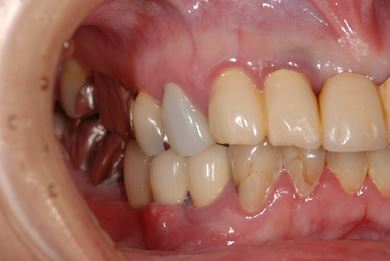

インプラントの症例写真 IMPLANT

骨再生インプラント治療

| 主訴 | 右下のブリッジが外れているかもしれないという診断を受けましたが、開けてみないとわからない、場合によっては部分入れ歯と言われ、セカンドオピニオンを希望。腫れがあるのも気になります。 | ||||||||||||||||||||||||||||||||

| 治療方針 | 右下奥、骨再生法によりインプラント治療を可能にする。 | ||||||||||||||||||||||||||||||||

| 治療内容 | インプラント3本(GBR、テンポラリーインプラント+仮歯)、ハイブリッドセラミックブリッジ3本、ハイブリッドセラミッククラウン2本 | ||||||||||||||||||||||||||||||||